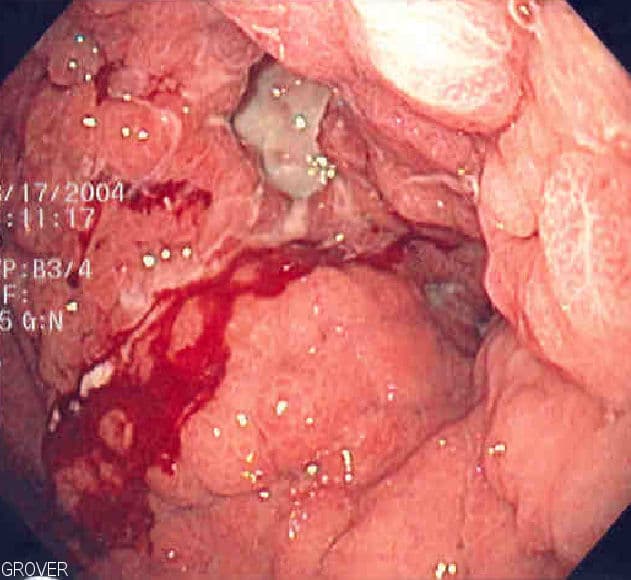

Stomach cancer, also known as gastric cancer, is a cancer that develops from the lining of the stomach. Most cases of stomach cancers are gastric carcinomas, which can be divided into a number of subtypes, including gastric adenocarcinomas. Lymphomas and mesenchymal tumors may also develop in the stomach. Early symptoms may include heartburn, upper abdominal pain, nausea, and loss of appetite. Later signs and symptoms may include weight loss, yellowing of the skin and whites of the eyes, vomiting, difficulty swallowing, and blood in the stool, among others. The cancer may spread from the stomach to other parts of the body, particularly the liver, lungs, bones, lining of the abdomen, and lymph nodes. The most common cause is infection by the bacterium Helicobacter pylori, which accounts for more than 60% of cases. Certain types of H. pylori have greater risks than others. Smoking, dietary factors such as pickled vegetables and obesity are other risk factors. About 10% of cases run in families, and between 1% and 3% of cases are due to genetic syndromes inherited such as hereditary diffuse gastric cancer. Most of the time, stomach cancer develops in stages over years. Diagnosis is usually by biopsy done during endoscopy. This is followed by medical imaging to determine if the disease has spread to other parts of the body. Japan and South Korea, two countries that have high rates of the disease, screen for stomach cancer. A Mediterranean diet lowers the risk of stomach cancer, as does the stopping of smoking. Tentative evidence indicates that treating H. pylori decreases the future risk. If stomach cancer is treated early, it can be cured. Treatments may include some combination of surgery, chemotherapy, radiation therapy, and targeted therapy. For certain subtypes of gastric cancer, cancer immunotherapy is an option as well. If treated late, palliative care may be advised. Some types of lymphoma can be cured by eliminating H. pylori. Outcomes are often poor, with a less than 10% five-year survival rate in the Western world for advanced cases.